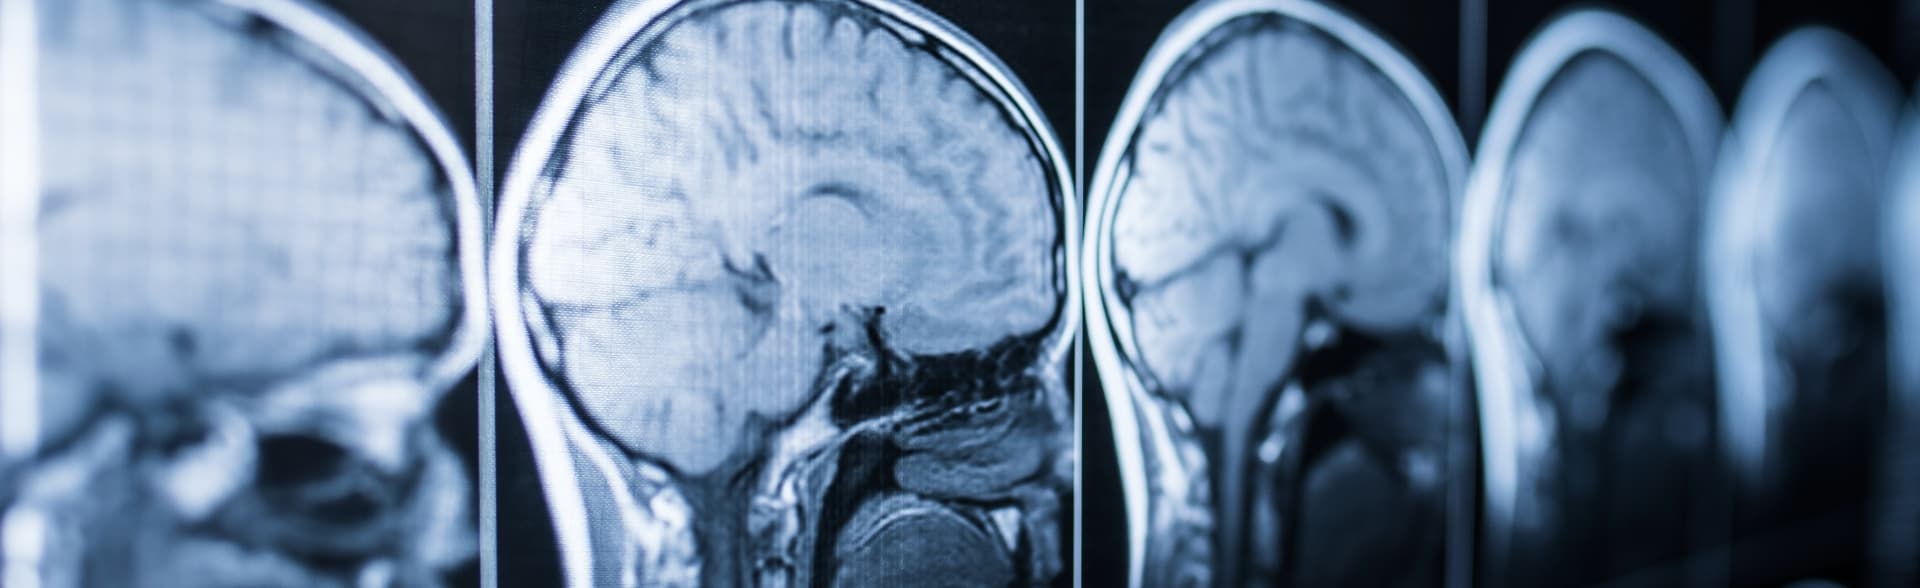

Neurocirugía

Experiencia en las principales enfermedades del sistema nervioso central como hidrocefalia, tumores, trauma craneoencefálico, aneurismas, entre otras. Formación en centros de referencia nacional para tumores cerebrales y trauma craneoencefálico.